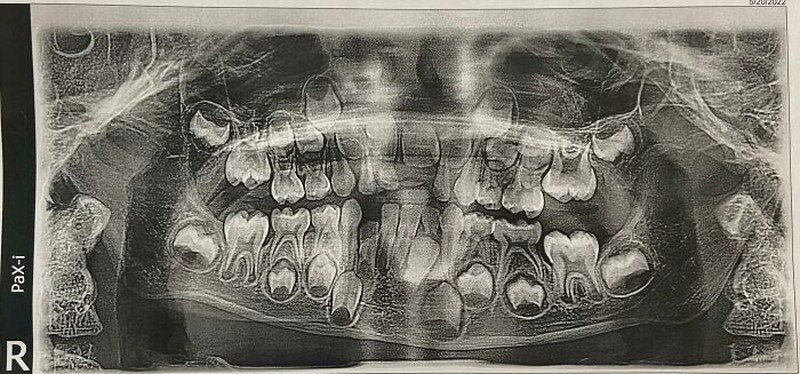

Foto Rontgen Gigi Anak yang Berusia 6 Tahun Foto: Boredpanda